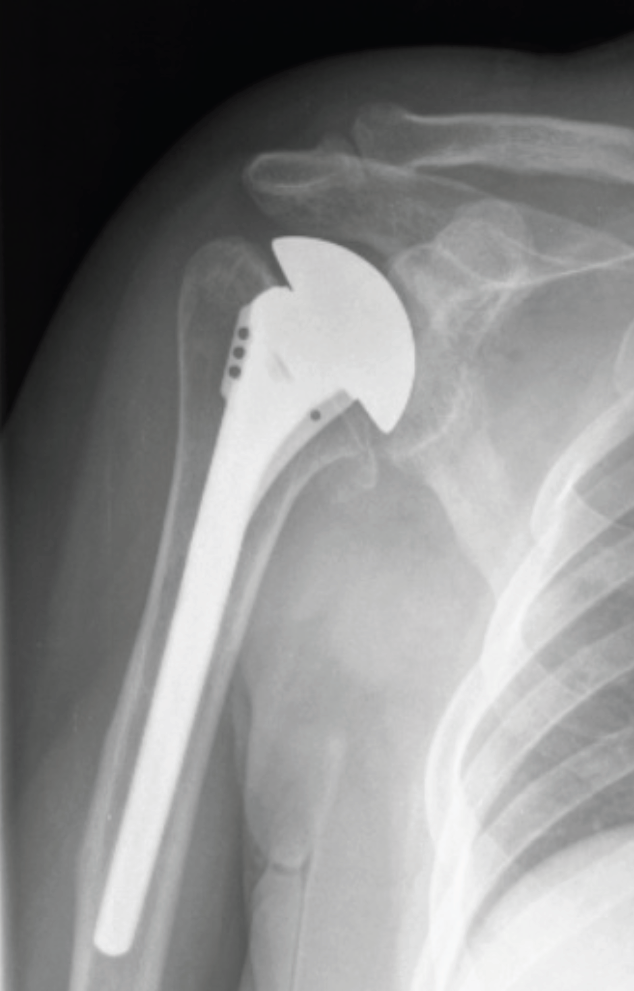

Kısmi Omuz Protezi: Yuvanın (glenoid) sağlam olduğu kol kemiğinin başı veya yumuşak dokunun hasarlı olduğu durumlarda yapılır. Yani bu protez tipinde omuz ekleminin yarısı değiştirilir. Glenoid denilen eklem yuvasına protez parçası yerleştirilmez. Kısmi omuz protezi daha çok parçalı humerus üst uç kırıklarının tedavisinde tercih edilir. Ayrıca glenoidde ciddi şekilde kemik zayıflığı olanlarda ve ciddi derecede yırtık rotator manşet tendonları ve artriti olan bazı omuzlarda kısmi omuz protezi ameliyatı yapılır.

Kısmi omuz protezi. Burada humerus başı total olarak değiştirilir.